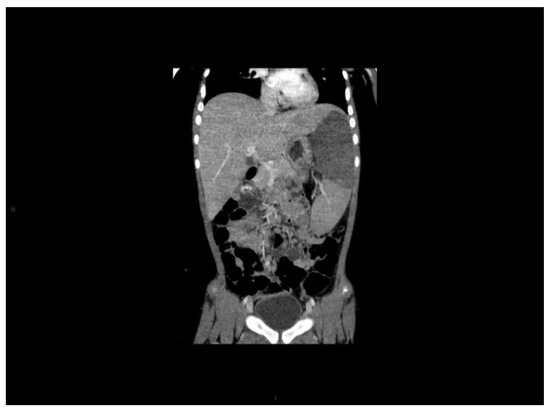

10. Clinical Features and Hematological Findings

- spleen size, liver size (both in cm below the costal margin) on quiet breathing,

- assessment of extramedullary manifestation of CML (lymph nodes, skin, bone, etc.),